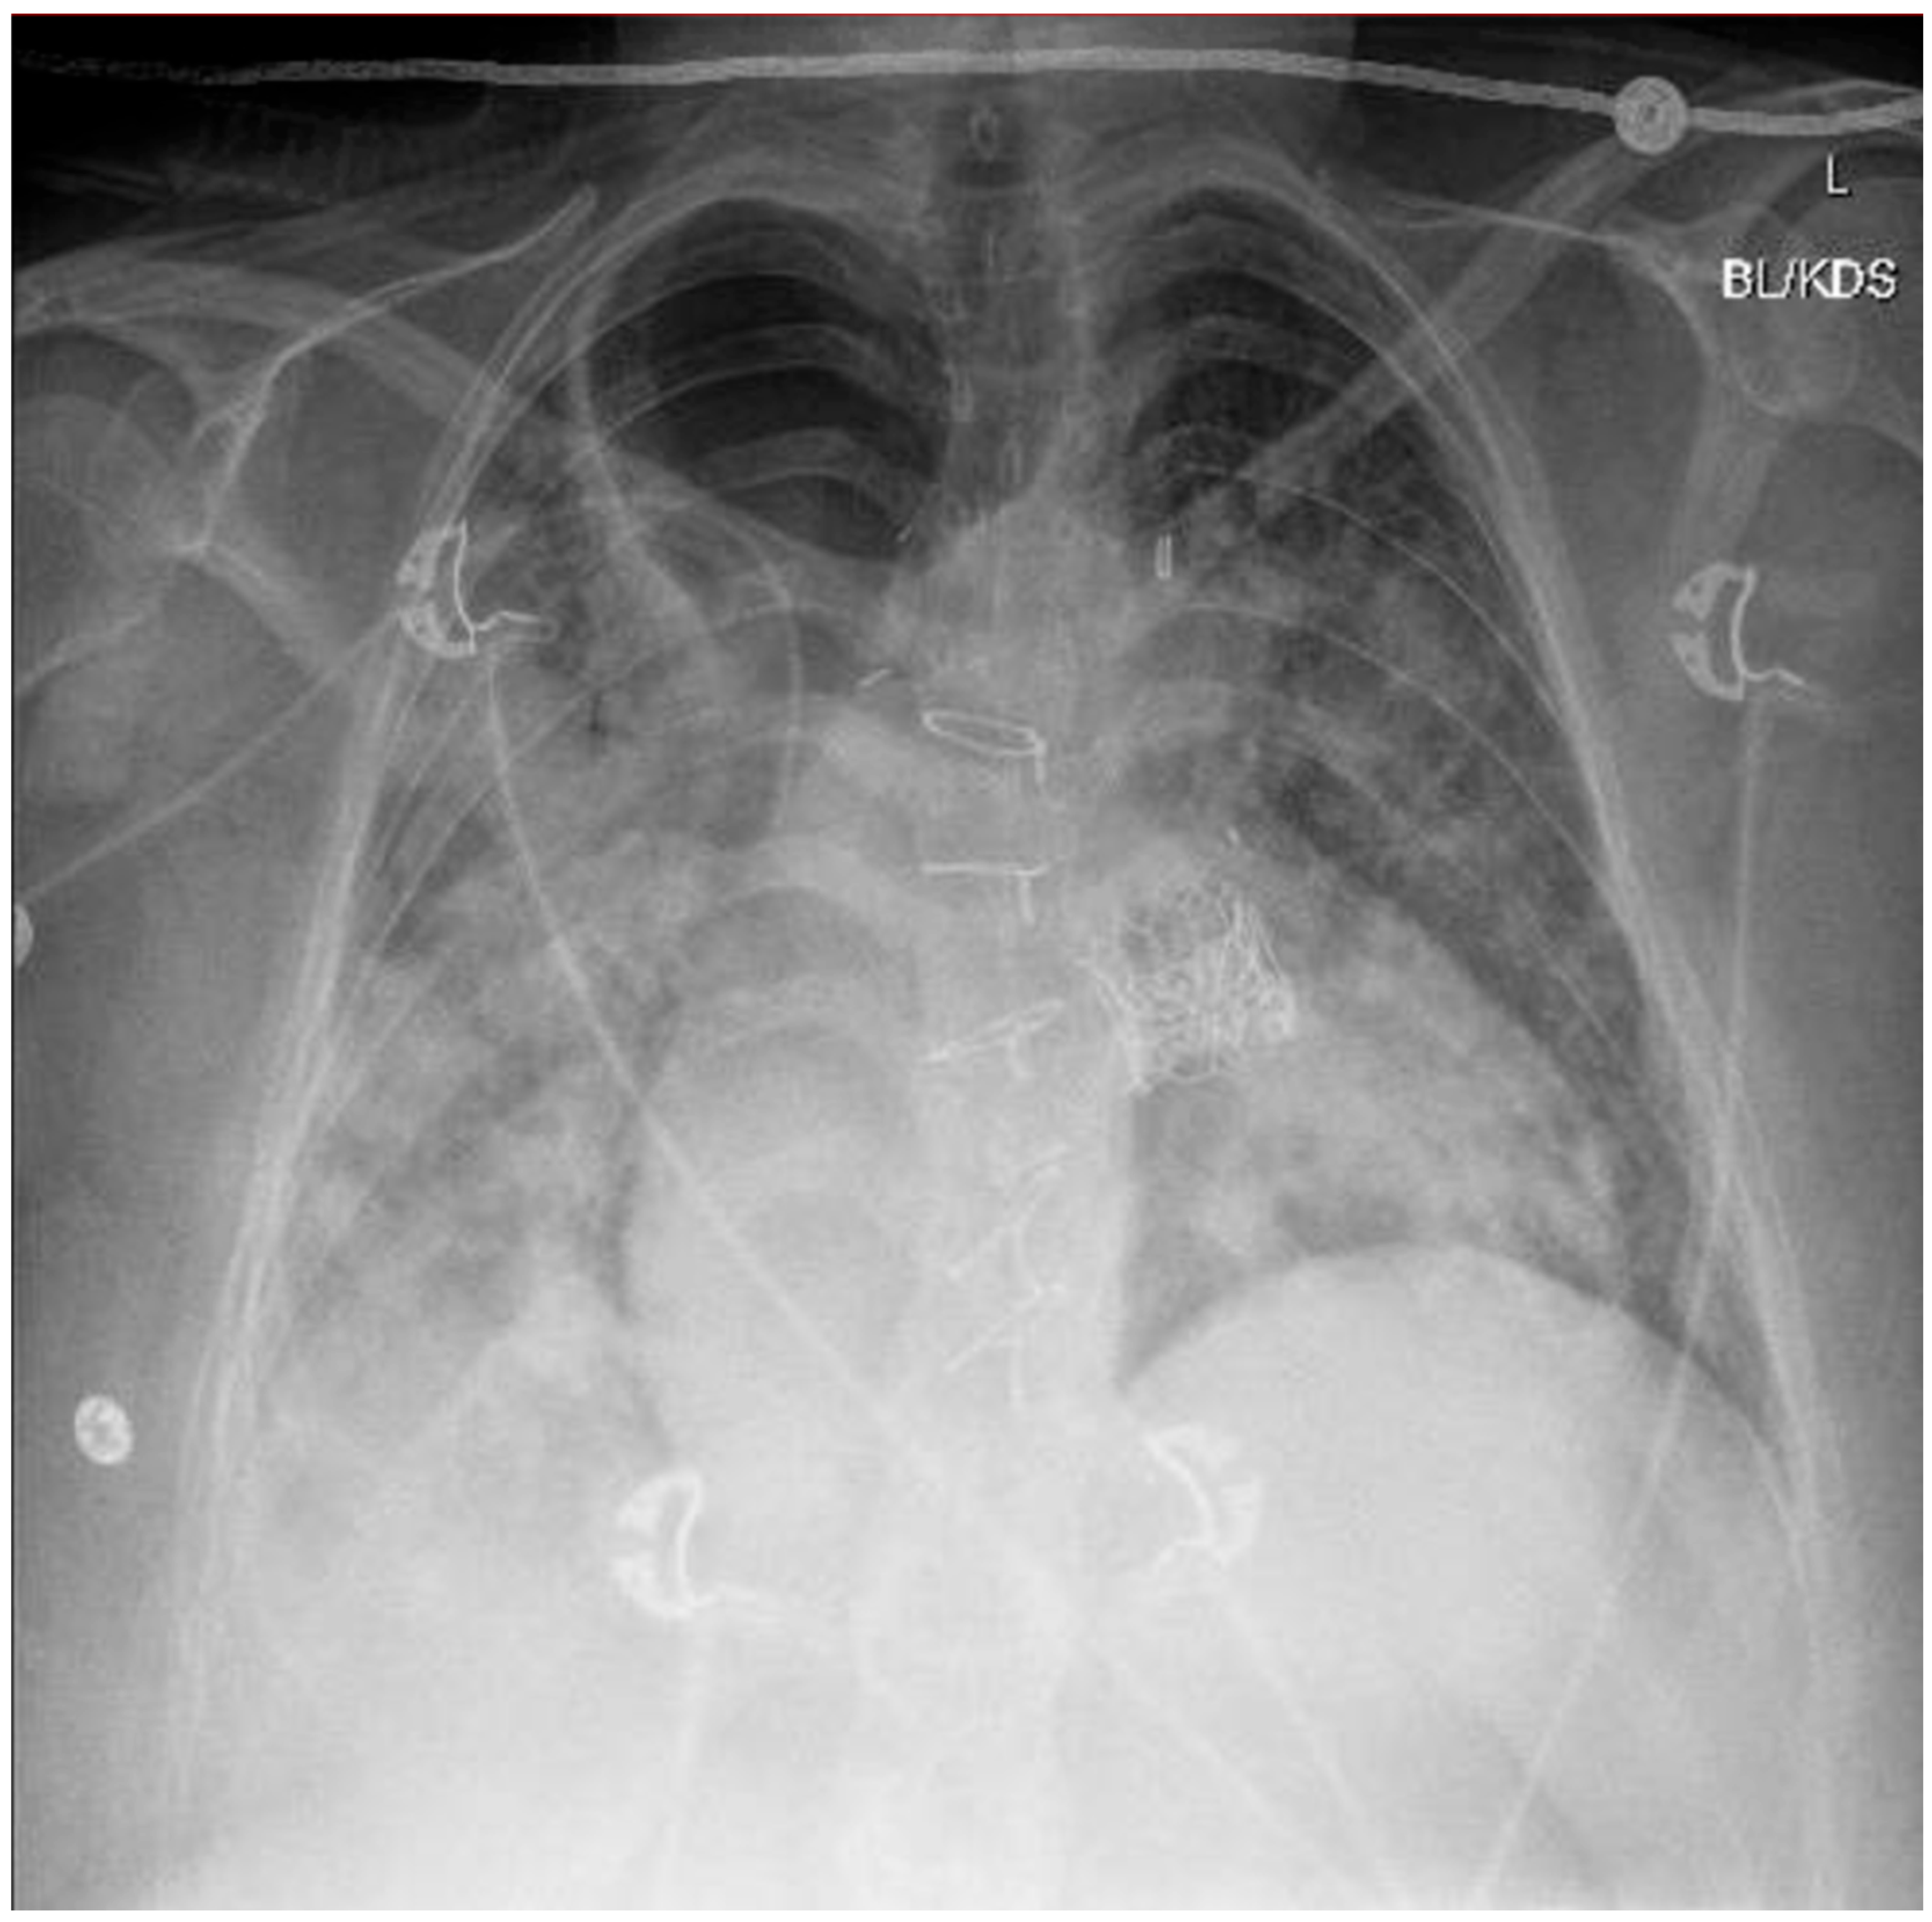

A chest X-ray and point-of-care ultrasound revealed diffuse bilateral airspace opacities and B-lines without consolidation, consistent with flash pulmonary edema (Figure 1). LRS—an uncommon complication characterized by non-cardiogenic pulmonary edema following sudden restoration of forward flow—was strongly suspected. Echocardiography excluded pulmonary embolism and right heart failure. Bronchoscopy revealed dense mucoid and sanguineous clots in the right upper lobe without purulence. Despite concern for aspiration, an infectious etiology was considered unlikely based on negative cultures, the lack of a fever, and rapid resolution of leukocytosis (initial WBC 27 × 109/L).

Approximately 3.5 h post-TPVR, the patient developed acute hypoxia and hypotension. A chest X-ray and point-of-care ultrasound revealed bilateral airspace opacities and B-lines without consolidation—findings consistent with flash pulmonary edema. LRS, a rare but serious complication resulting from the abrupt restoration of forward flow through a previously obstructed or stenotic valve, was strongly suspected. The underlying pathophysiology involves capillary leakage, oxidative stress, and alveolar flooding [10,11]. Echocardiography excluded pulmonary embolism and right heart failure. Bronchoscopy showed mucoid and sanguineous clots without purulence, and all cultures remained negative. Although aspiration was initially considered, especially given the patient’s history of achalasia, the lack of fever and rapid clinical improvement with diuresis made this less likely.

Figure 1. Postop chest X-ray (CXR) revealing increased multifocal airspace opacities most prominent in the right lung with a mediastinal shift and diffuse bilateral reticular opacities indicative of Lung Reperfusion Syndrome. Additionally median sternotomy wires from previous coronary artery bypass grafting (CABG) and TAVR can be noted.